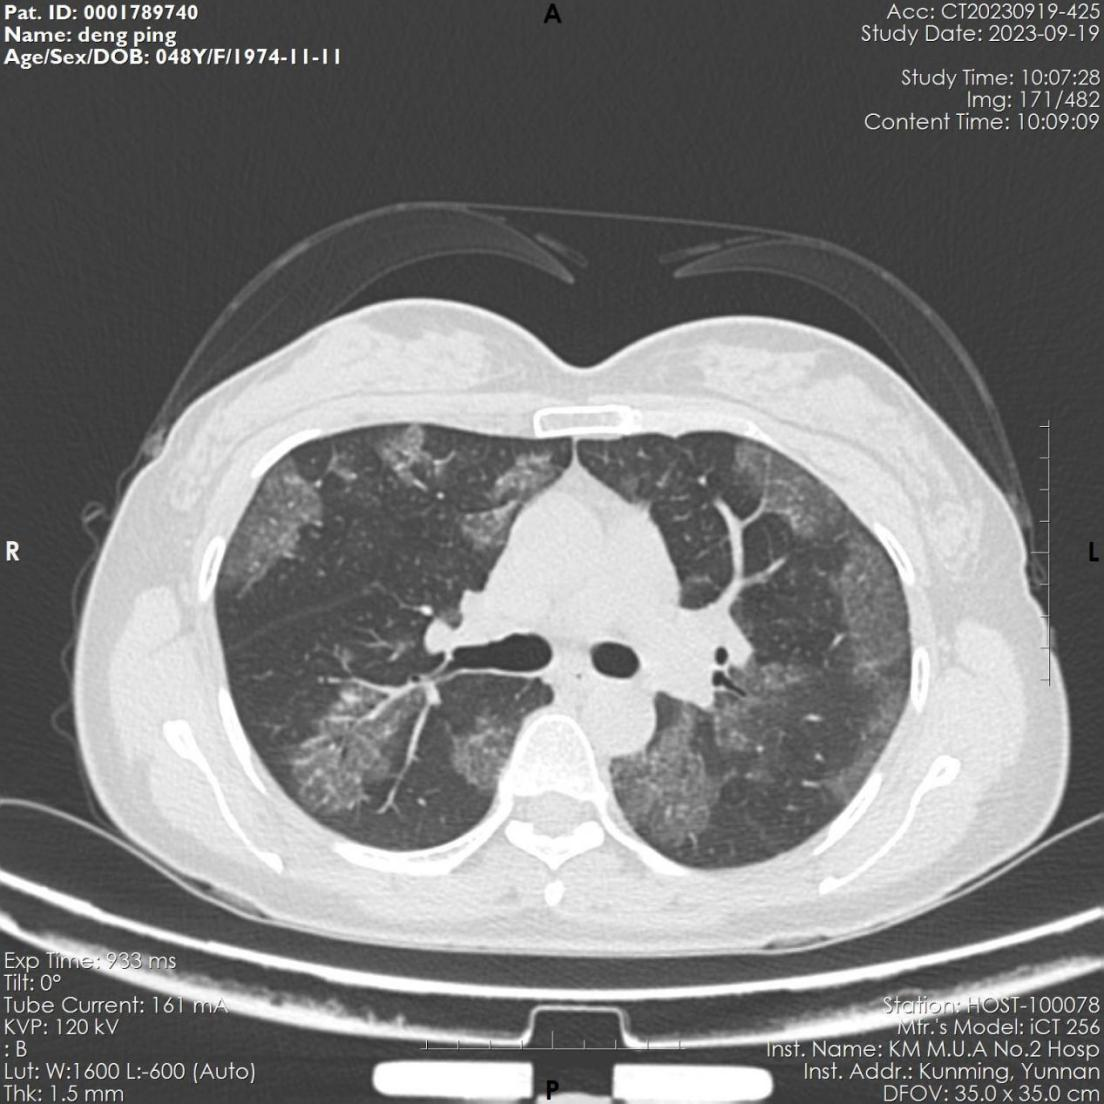

该患者,女,48岁,近3月来反复出现活动后胸闷气促。6月份因感染肺炎住院治疗,经抗病毒治疗后,咳嗽、咽痛等呼吸道症状缓解。9月因胸闷气促再发加重,来到樱花动漫 全科医学科就诊,复查胸部CT显示肺部病变未见吸收,病变呈弥漫磨玻璃影,病变与正常组织分界较清,呈“地图征”,考虑“间质性肺疾病-肺泡蛋白沉积症可能”收住全科医学科。入院后完善电子支气管镜检查示双侧支气管未见明显异常,但各管腔内的肺泡灌洗液呈乳白色,肺泡灌洗液细胞学病理检查示肺泡巨噬细胞中间粉红色颗粒样物质,D-PAS和PAS染色阳性。结合病史、胸部CT、肺泡灌洗液呈乳白色、PAS染色阳性,该患者确诊罕见病“肺泡蛋白沉积症”。